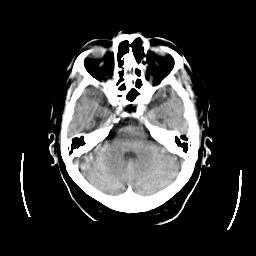

CT Study #2 -- Slice #8